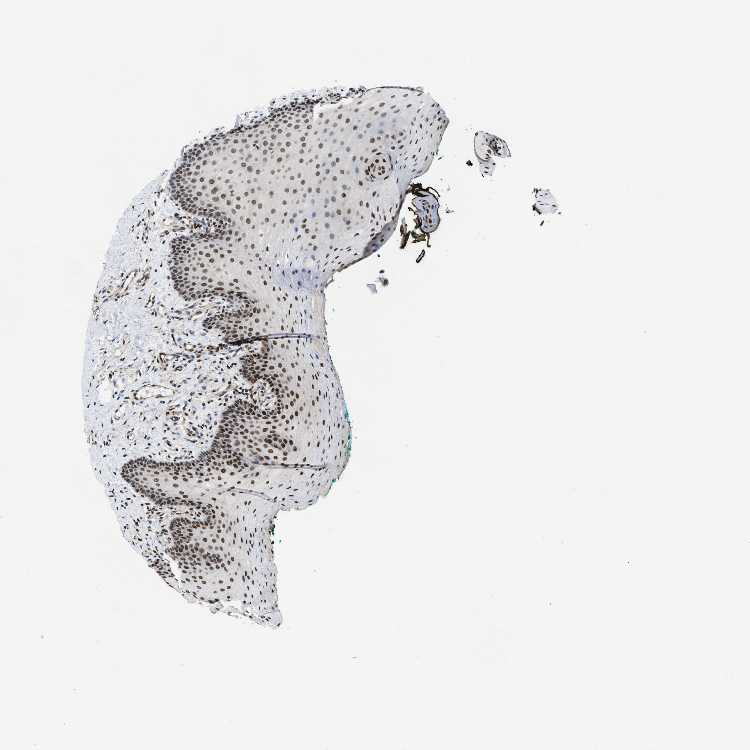

TISSUE PRIMARY DATA ORAL MUCOSA Show tissue menu

ORAL MUCOSA - Antibody stainingi

Antibody staining in the annotated cell types in the current human tissue is reported as not detected, low, medium, or high, based on conventional immunohistochemistry profiling in selected tissues. This score is based on the combination of the staining intensity and fraction of stained cells.

Each image is clickable and will lead to virtual microscopy that enables deeper exploration of all samples and also displays staining intensity scores, fraction scores and subcellular localization as well as patient and tissue information for each sample.

Antibody HPA016832Antibody HPA020076Antibody CAB001969

Squamous epithelial cells HighHighHigh